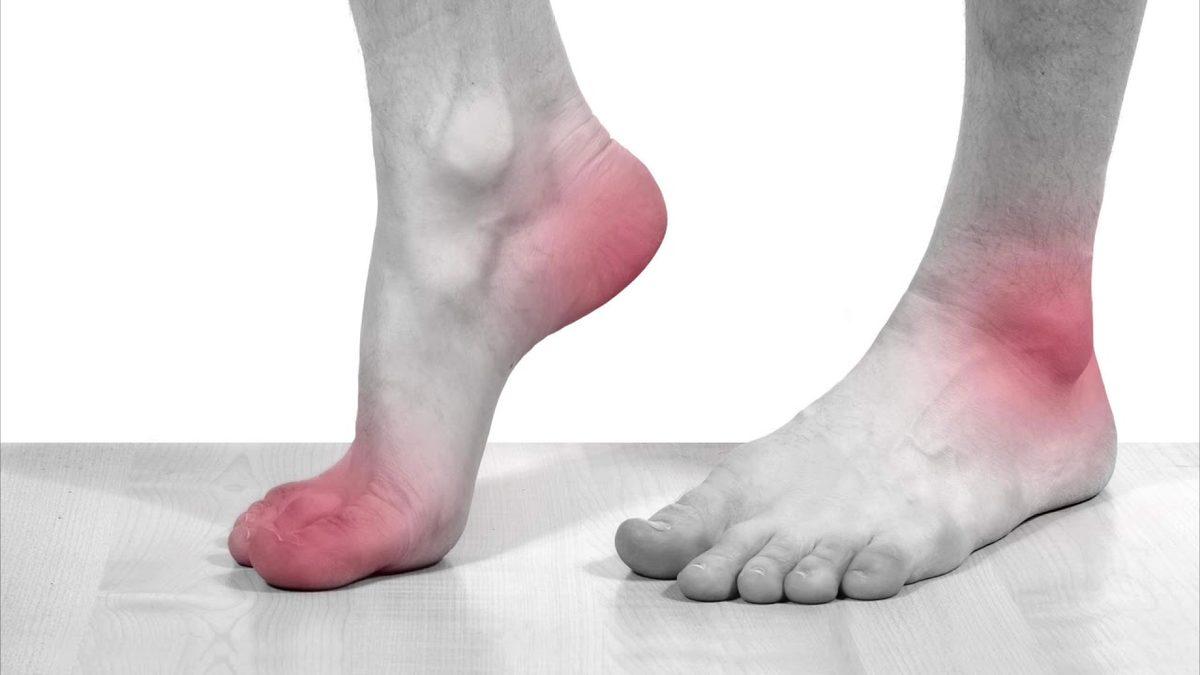

Gut atağı bir anda başlar. Hasta ya uykusundan uyanacak kadar güçlü bir ağrı hisseder ya da uyandığı zaman durumu fark eder. Ağrı başlamasından sonraki 4 ile 12 saat arasında ağrı artacaktır. Atak bölgesinde şişlik, kızarıklık, ağrı ve hassasiyet oluştuğu için hasta eklemlerini normal bir şekilde hareket ettiremez.

Gut atağının çoğu zaman ilk ortaya çıktığı yer ayak başparmağı eklemidir. Ayak bileği, diz ve ilerleyen zamanlarda omurga sisteminde bile iltihap oluşturabilir. Gut atağı her zaman eklemlerde meydana gelir çünkü ürik asit gece kan sıcaklığı azalınca eklemlerde toplanarak kristalize bir hal alır.